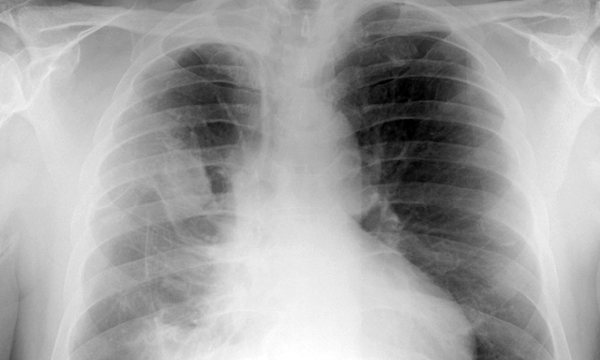

This is a summary of the peer-reviewed article: Abdominal X-rays in children: indications, proced